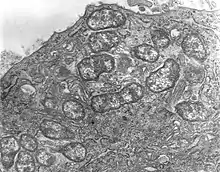

Orientia tsutsugamushi is a Gram-negative bacterium and is a permanent (obligate) parasite in mites. Within a single host cell, O. tsutsugamushi rapidly divides into many individuals as shown in Figure 1. A unicellular organism, it is oval shaped and measures 0.5 to 0.8 µm wide and 1.2 to 3.0 µm long. Due to similarity, it was previously classified in the genus Rickettsia among other bacteria, but later assigned a separate genus, Orientia,[20] which it shares (as of 2010) only with Candidatus Orientia chuto.[21] It is broader but shorter than other rickettsial bacteria, which are rod shaped and on average measure 0.25 to 0.3 µm wide and 0.8 to 1 µm long.[22] During reproduction, it divides (by binary fission) into two daughter cells by the process of budding. While undergoing budding, it accumulates on the host cell surface, unlike other bacteria. One complete budding cycle takes 9 to 18 hours.[23]

The structure of O. tsutsugamushi (revealed by transmission electron microscopy) is shown in Figure 2. The bacterium is enclosed by a cell wall on the outside and cell membrane on the inside. The cell covering takes up stains such as Giemsa and Gimenez stains. Although its cell wall has a classic bacterial double layer, its outer leaflet is much thicker than the inner one, which is just the opposite in Rickettsia species.[24] A capsule layer that forms a spherical halo in other bacteria is missing. The cell wall is less rigid due to the absence of peptidoglycan, which is otherwise characteristic of the rigid cell walls of other bacteria. Classic bacterial lipophosphoglycans such as muramic acid, glucosamine, hydroxy fatty acids, heptose, and 2-keto-3-deoxyoctonic acid are also absent in the cell wall. Due to the absence of peptidoglycan, the bacterium is naturally resistant to all β-lactam antibiotics (such as penicillin), to which Rickettsia species are normally sensitive to.[25] Its genome totally lacks the genes for lipophosphoglycan synthesis, but does contain some for those of peptidoglycan. Important genes essential for peptidoglycan synthesis such as alr, dapF and PBP1 are missing: alr encodes an enzyme L-alanine racemase, which converts L-alanine to D-alanine in the first step of peptidoglycan synthesis pathway; dapF encodes diaminopimelate epimerase, which convert LL-2,6-diaminoheptanedioate (L,L-DAP) to meso-diaminoheptanedioate (meso-DAP); and PBP1 encodes penicillin-binding protein-1 (PBP1), which converts periplasmic lipid II to peptidoglycan. Thus, the bacterium cannot synthesise a typical peptidoglycan cell wall, and instead makes a peptidoglycan-like structure on its surface.[26] The cell membrane is also chemically different in its protein composition, and this difference gives rise to strain variations within the species itself.[27] The cytoplasm is clear and shows distinct DNA and ribosomes.